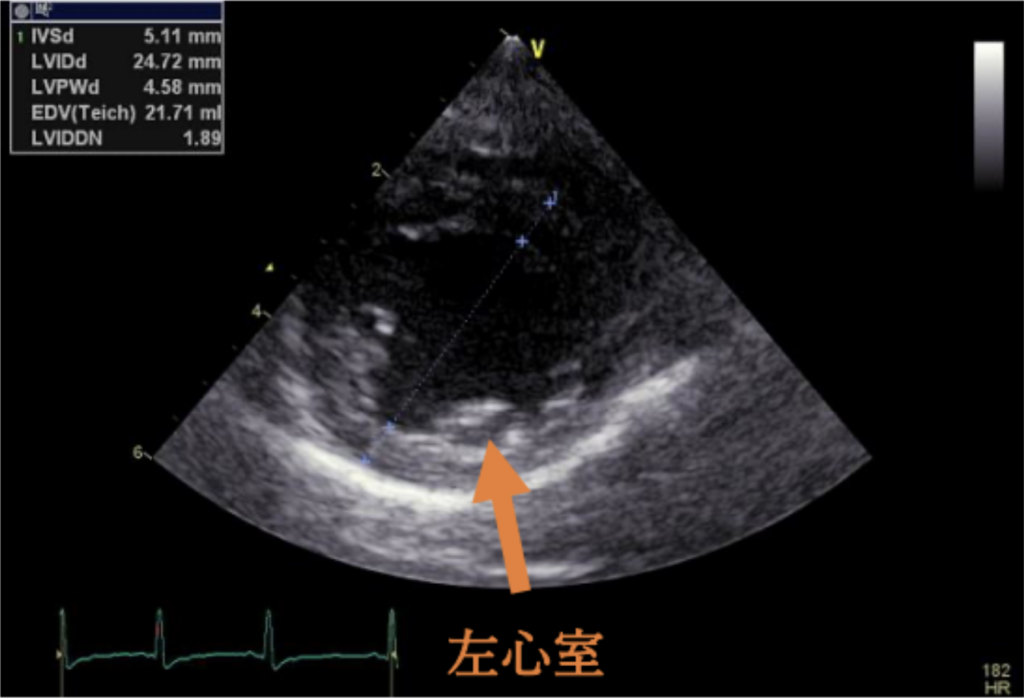

今回の⼼臓超⾳波検査では、僧帽弁からの⾎液の逆流が以前よりも増えており、⼼臓が

拡⼤してきていることが確認されました。そのため、⼼臓の働きを助けて病気の進⾏を

遅らせる⽬的で、ピモベンダンというお薬の内服を始めることになりました。

心臓拡大を認める

内服開始